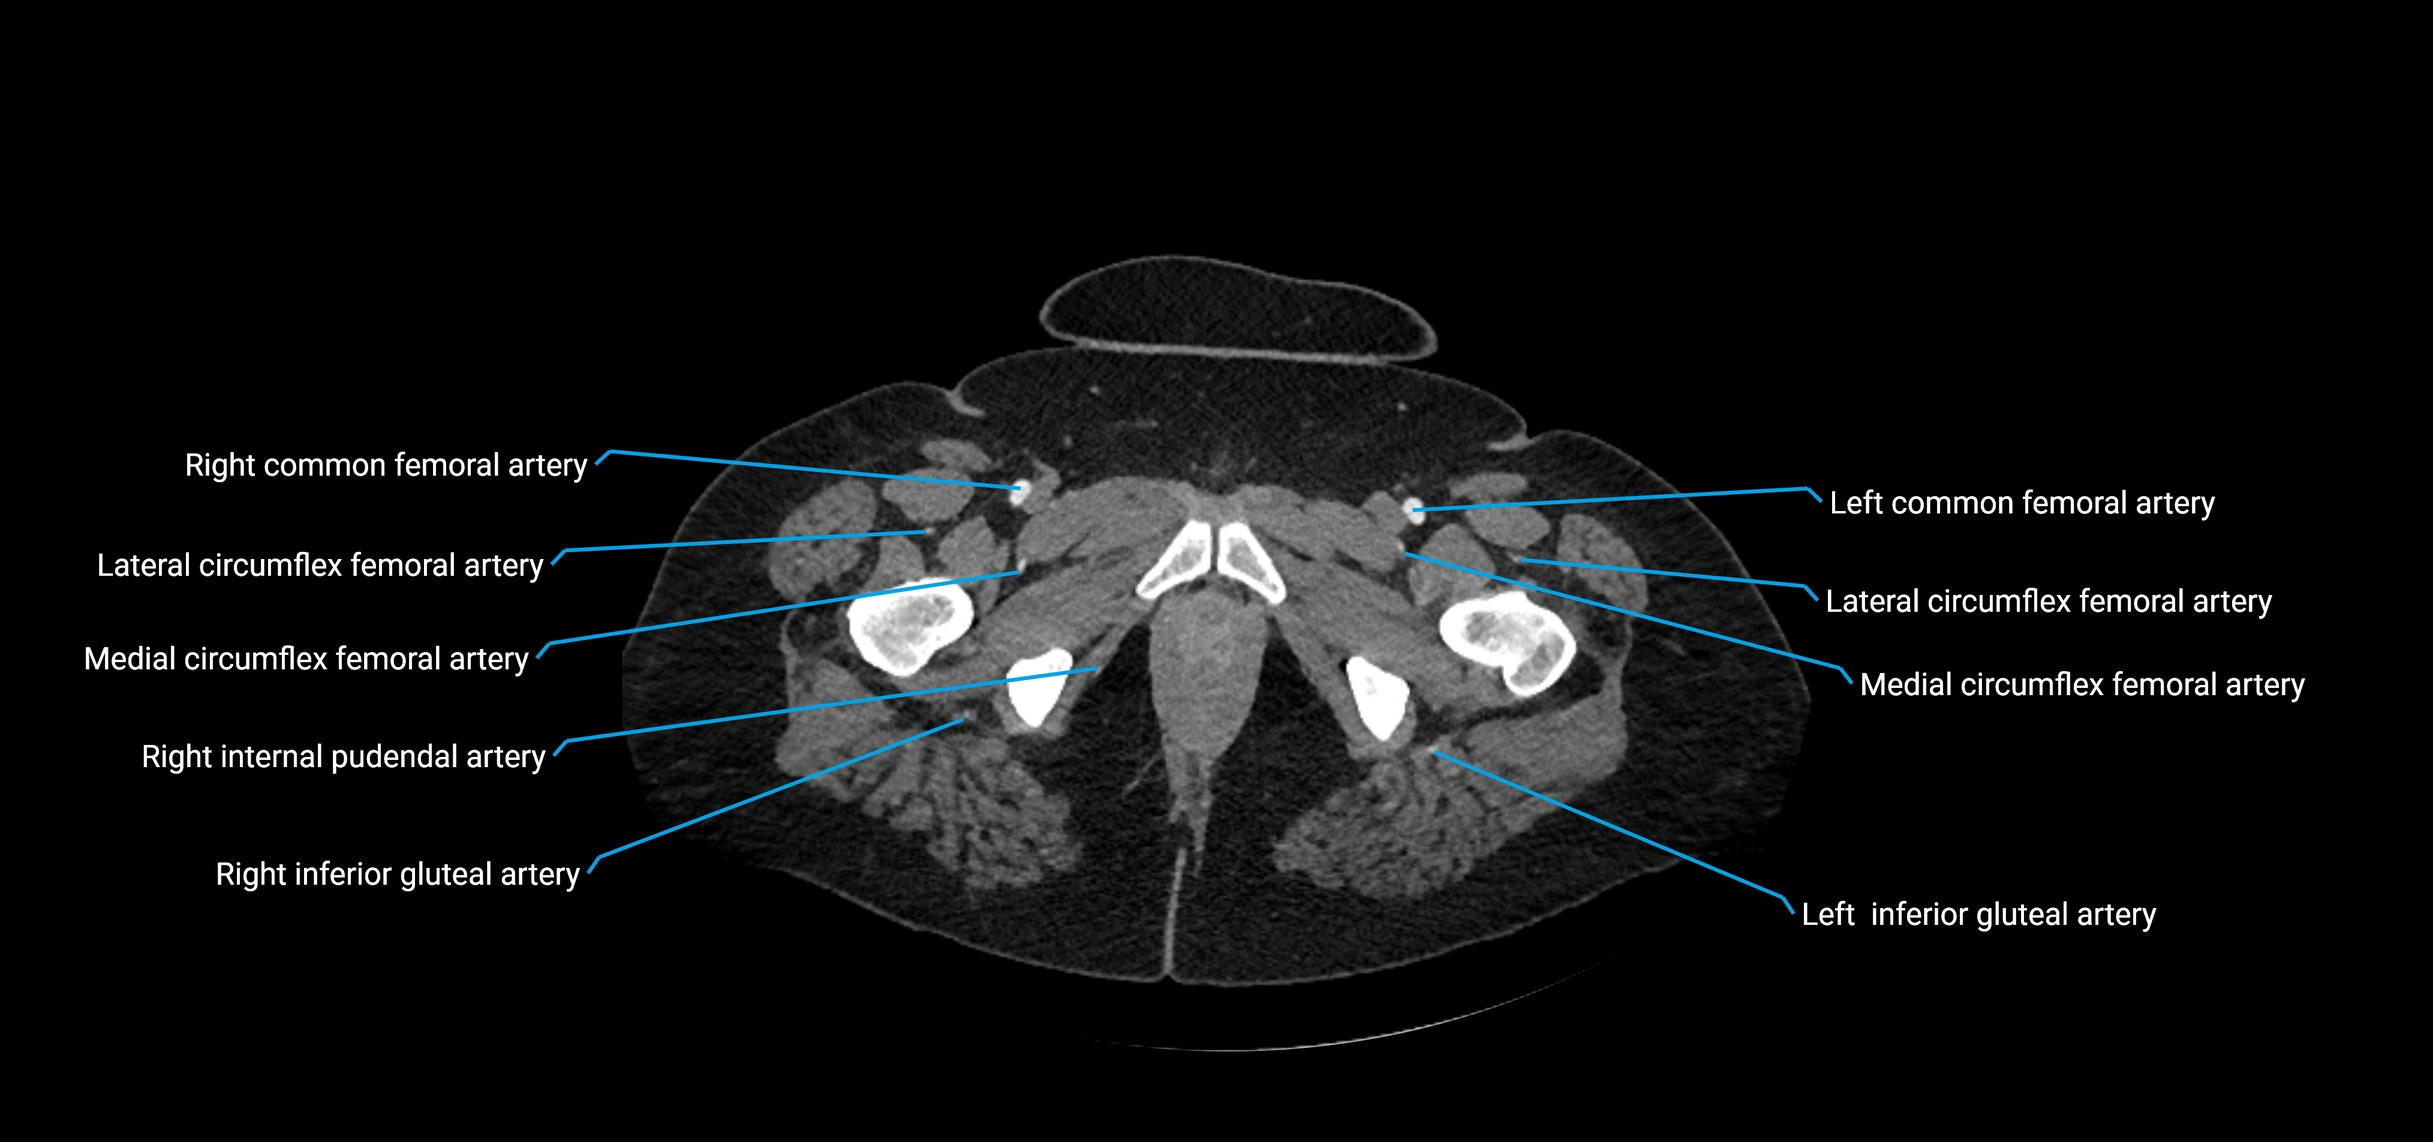

CT images

image

Contrast-enhanced CT (CTA):

• Gold standard for abdominal aortic imaging

• Provides excellent detail of lumen, wall, aneurysm, thrombus, and branch vessels

• Multiplanar and 3D reconstructions help in aneurysm measurement, stent graft planning, and dissection evaluation